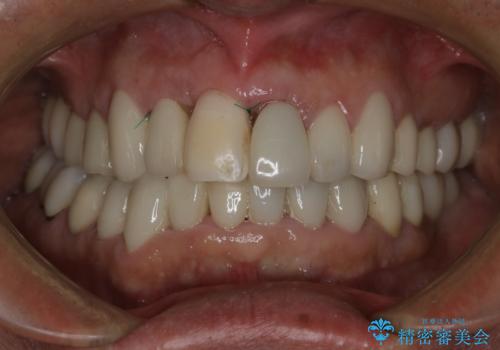

- 事故による外傷で前歯に歯根が真っ二つに折れてしまい、保存不可能となってしまった部分にインプラント治療を計画しました。

患者様のご要望もあり、審美性の確保ができる抜歯早期埋入→埋入後即時荷重という手術法を取りました。

それと比較すると、今回の方法では骨にしっかりと固定されているインプラントに単独で仮歯を装着することができるためフロスも通せますし、ある程度負荷のかかる食事も気にせずできるようになります。